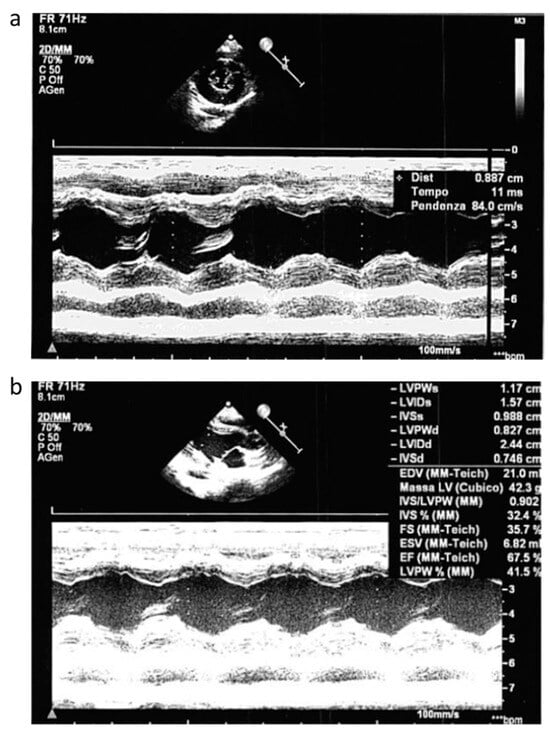

2.1. Clinical Characteristics